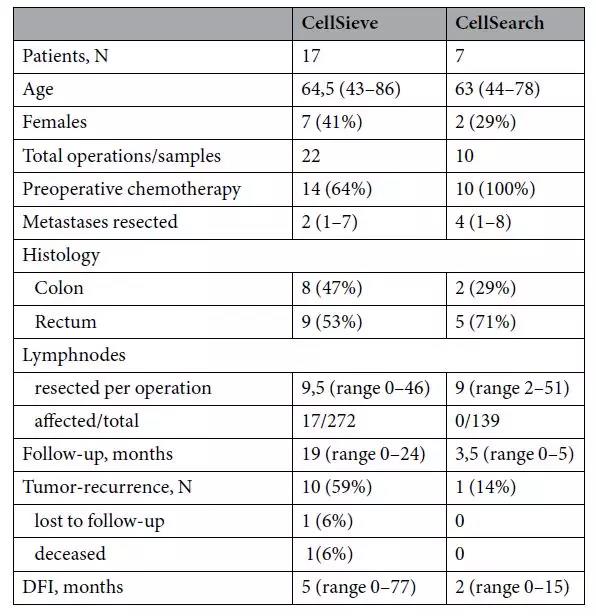

他们在24个结直肠癌肺转移瘤切除手术中,采集了转移癌病侧肺静脉血液。他们采用CellSieve-microfilters技术、免疫组织化学和Giemsa染色,对22个标本进行了枚举CTC检测。另外10个血液标本采用CellSearch-System进行分析。他们从肺静脉中枚举到癌细胞数(总计41,在0-15个范围),远远超过同时在肢体血管采血检测到的癌细胞数(总计6个,在0-5个范围,P=0.009)。在所有检测到CTC病例中,研究人员发现,肺静脉血中的癌细胞与肺转移结直肠癌导致局部淋巴侵犯有显著相关性(P=0.006),也就是说结直肠癌肺转移,并发肺部淋巴结转移的病人,肺静脉内更容易筛查到癌细胞。

表示:临床、手术和随访数据.连续的数据显示的是中位数,计数数据为频率和百分数。